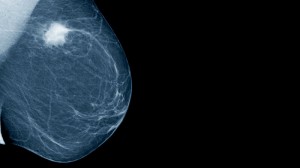

A mammogram is an X-ray picture of the breast, and there is no shortage of proponents who refer to the mammogram as “currently the most effective screening method of detecting breast cancer in its earliest, most treatable stages.” But anyone with half an ear bent toward the public debate over screening mammography in the past 15 years or so, especially a high profile journalist for a national media outlet, would know that the preponderance of evidence shows that the benefits of mammograms are much less than many of us want to believe. “Period, end of discussion” couldn’t be farther from the truth.